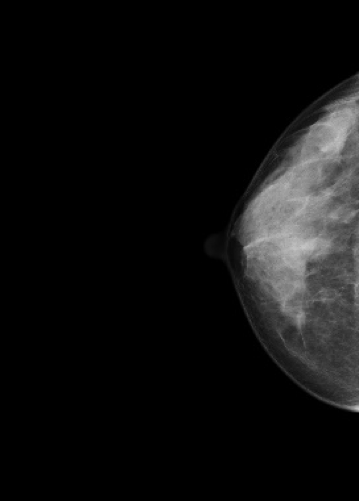

マンモグラフィ検査

装置の紹介

当院では2016年5月に乳房撮影装置

MAMMOREX Pe・ru・ru DIGITAL

(キヤノンメディカルシステムズ)を導入しました。

FPDを搭載した装置で、解像力やコントラストが向上し微細な石灰化や腫瘤をより鮮明に描出することが可能です。検査は健診棟の女性専用エリア内に併設されたマンモグラフィ専用の検査室で行っており、安心して検査を受けていただけます。撮影はNPO法人日本乳がん検診精度管理中央機構の認定を受けた女性技師が担当します。

マンモグラフィとは

専用の装置を用いて行う乳房のX線撮影のことです。 マンモグラフィは視触診では分からない早期乳癌の微細な石灰化や、触っても分からない小さなしこりの描出に優れています。

*当院では左右の乳房それぞれで2方向の撮影(CC撮影・MLO撮影)を計4枚行います。

*2方向から撮影を行うことで乳房全体をまんべんなく写すことができます。

圧迫の必要性

厚みのある乳房の中にはたくさんの乳腺や脂肪などが重なって存在しています。

これらを均等に伸ばし組織同士の重なりを分離することで、小さなしこりや石灰化の粒をより見つけやすい画像にすることができます。

*実際に乳房を圧迫する時間は1枚の撮影で数十秒程度です。

画像1枚目:圧迫なし、画像2枚目:圧迫あり